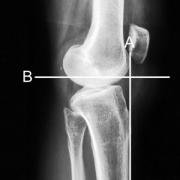

Then a line is drawn perpendicular to the anterior tibial cortex line (B). Finally a line is drawn along the top of the tibial plateau (C), and the angle of the posterior tibial slope is the angle formed by B and C.